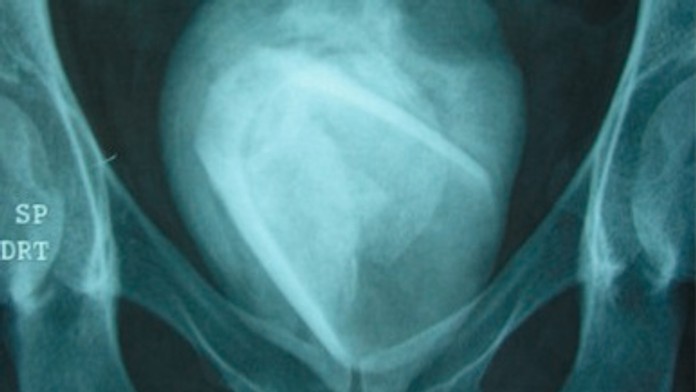

Röntgenová snímka odhalila cudzí predmet. Zdroj: sciencedirect.com

Pacientka (45) sa sťažovala, že má príznaky, ktoré zodpovedajú tejto chorobe. Okrem iných spomínala aj inkontinenciu. Keď však lekári urobili röntgenovú snímku, ostali prekvapený. V močovom mechúre spozorovali obrysy cudzieho predmetu.

Žena podstúpila operáciu, pri ktorej jej z močového traktu odstránili nezvyčajne veľký močový kameň. To ale nebolo posledný šok, ktorý zažili. Keď kameň s priemerom 8 centimetrov rozpolili, našli v ňom sklenený štamperlík.

Močový kameň so štamperlíkom v jadre. Zdroj: sciencedirect.com

„Pacienti si do močového traktu vkladajú rôzne predmety za účelom erotického potešenia, no potom ich nevedia vybrať von. Hanbia sa vyhľadať lekársku pomoc a potom sa stáva napríklad aj to, čo môžeme vidieť na röntgenovej snímke,“ uvádza sa v publikácii.